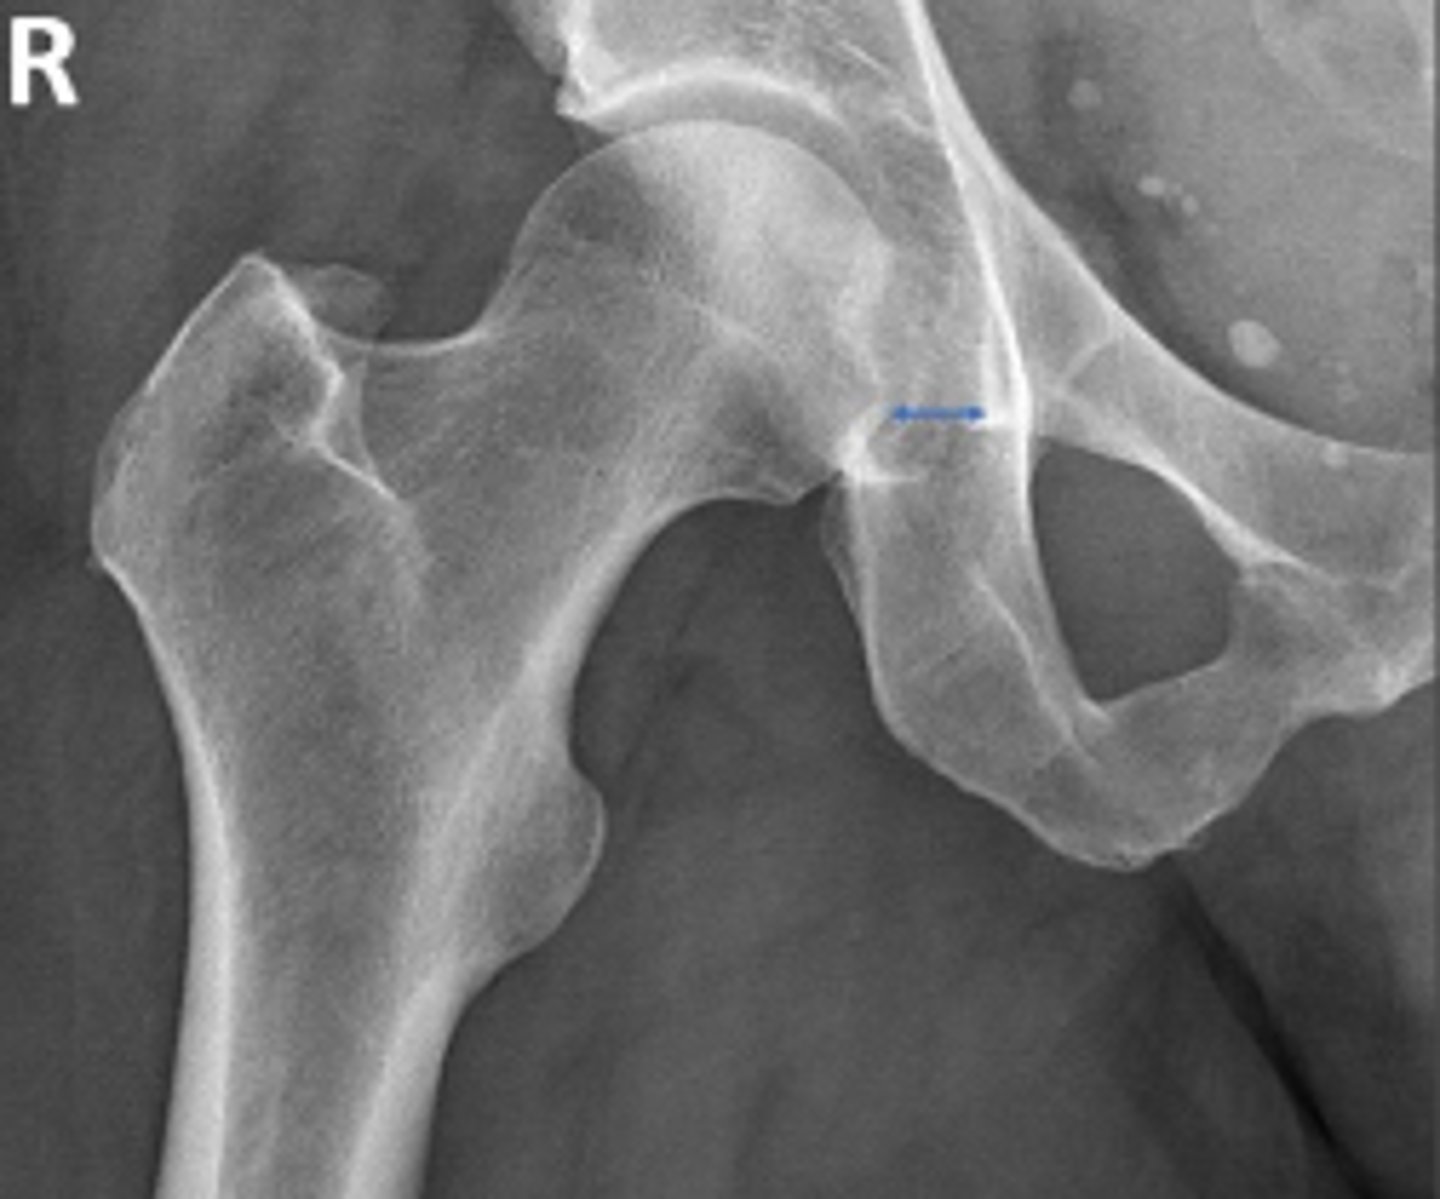

Hip joint space width

What is the name of the assessment?

Superior joint space is 3-6mm

Axial joint space is 3-7mm

Medial joint space is 4-13mm

What is the normal range for this assessment?

Superior joint space-> The measurement between the most convex superior aspect of the femoral head and the adjacent acetabulum

Axial joint space -> The measurement between the

femoral head and the acetabulum lateral to the

acetabular notch

Medial Joint space -> The measurement between the most medial margin of the femoral head and the adjacent pelvic teardrop

What are the osseous landmarks for this assessment?

Yes

Are the measurements within normal limits?

Degenerative joint disease

Name 1 condition that may result in a measurement of <3mm for the superior joint space?

AP pelvis and AP hip views

Name 2 radiographic views for this assessment?